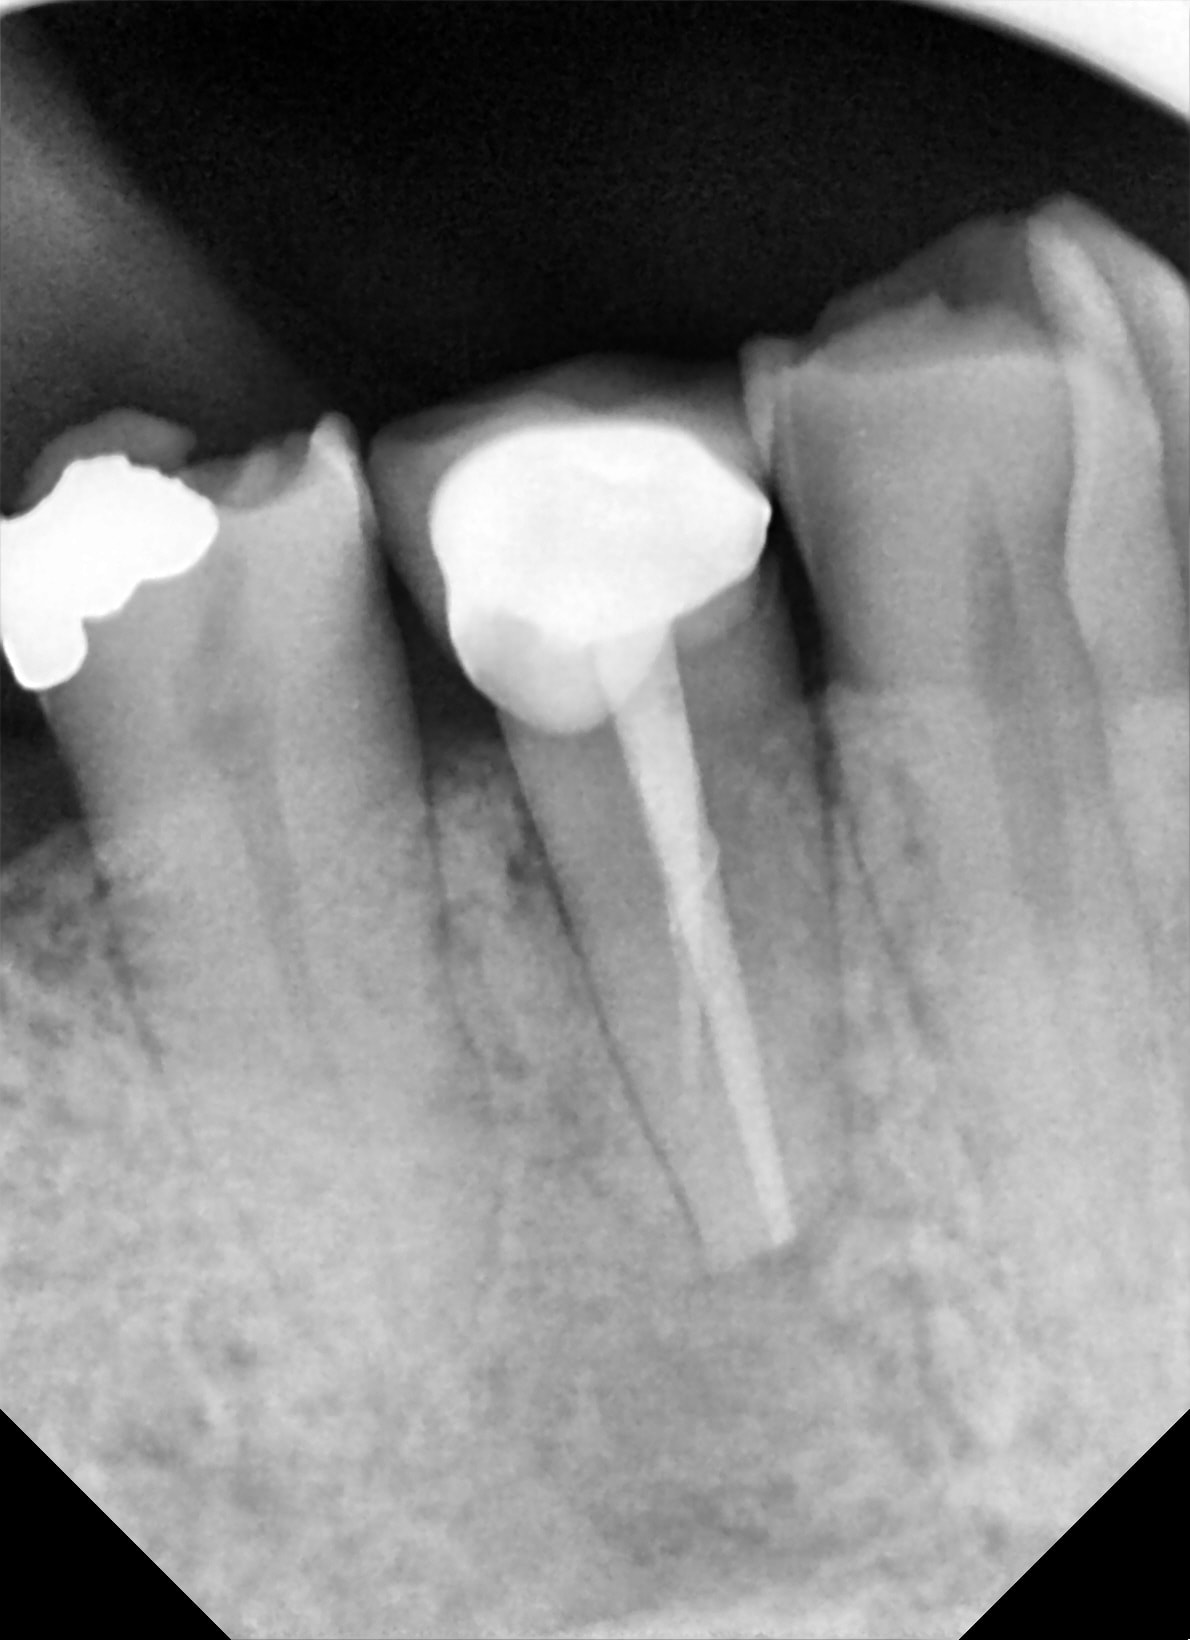

à 4 mois ménage + radio :

- à pu bobo

-à pu fistule

-à pu mobilité

un implant de moins !

bien justement la voilà la 37 , je l ai vu aujourdhui .

la radio est belle , , je n' arrive pas a la mettre dessus avec ces putains de enregistrer sous , sous quoi ? je ne sais pas ,

bref tu peux me faire confiance , et en photo ça donne ça .

la gencive est belle et j'ai pris l empreinte .

l'affaire est dans le sac !

merci enlaye!